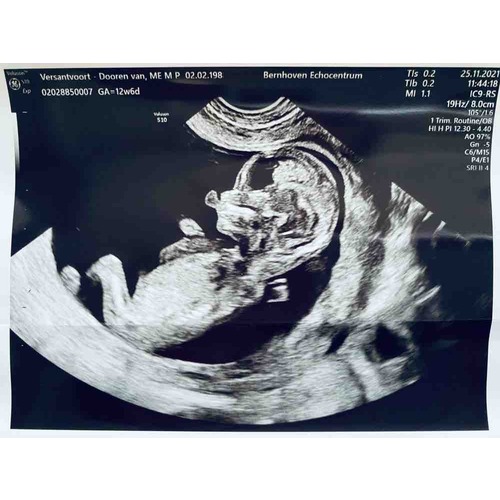

Wat denken jullie?馃グ馃挏 12wk6

Wat denken jullie 馃槉馃槉鉁ㄢ湪

Niet duidelijk